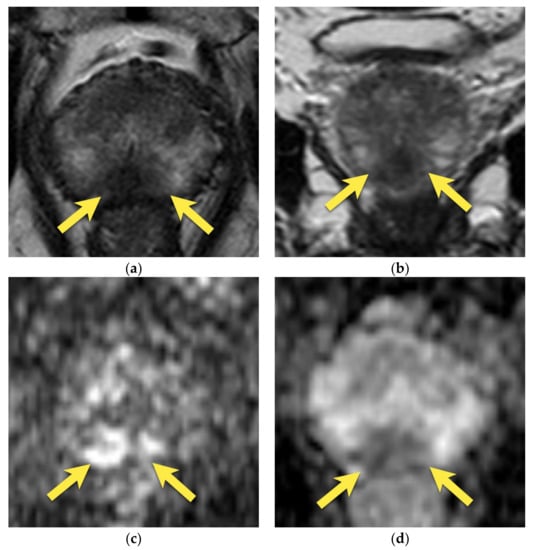

10. Prostatic Abscess